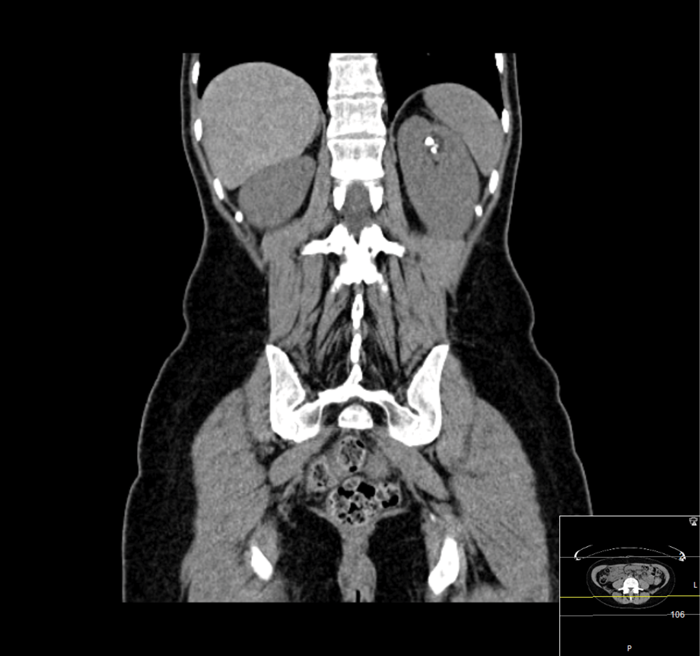

An 80-year-old woman presented with urosepsis requiring direct admission to intensive care. A CT scan demonstrated gas in the collecting system and a nephrostomy was inserted.

Figure 1: CT demonstrating gas in the collecting system.

Figure 2: Nephrostogram showing stone in left kidney with nephrostomy in place prior to flexible ureteroscopy.

The patient made a good recovery from her life-threatening sepsis, retaining function on a DMSA scan and underwent a flexible ureteroscopy to clear the stone. Gas forming organisms in the urinary tract result in dramatic imaging but should not distract from the patient’s clinical condition. A conservative approach may avoid a nightmare nephrectomy in a highly morbid patient.